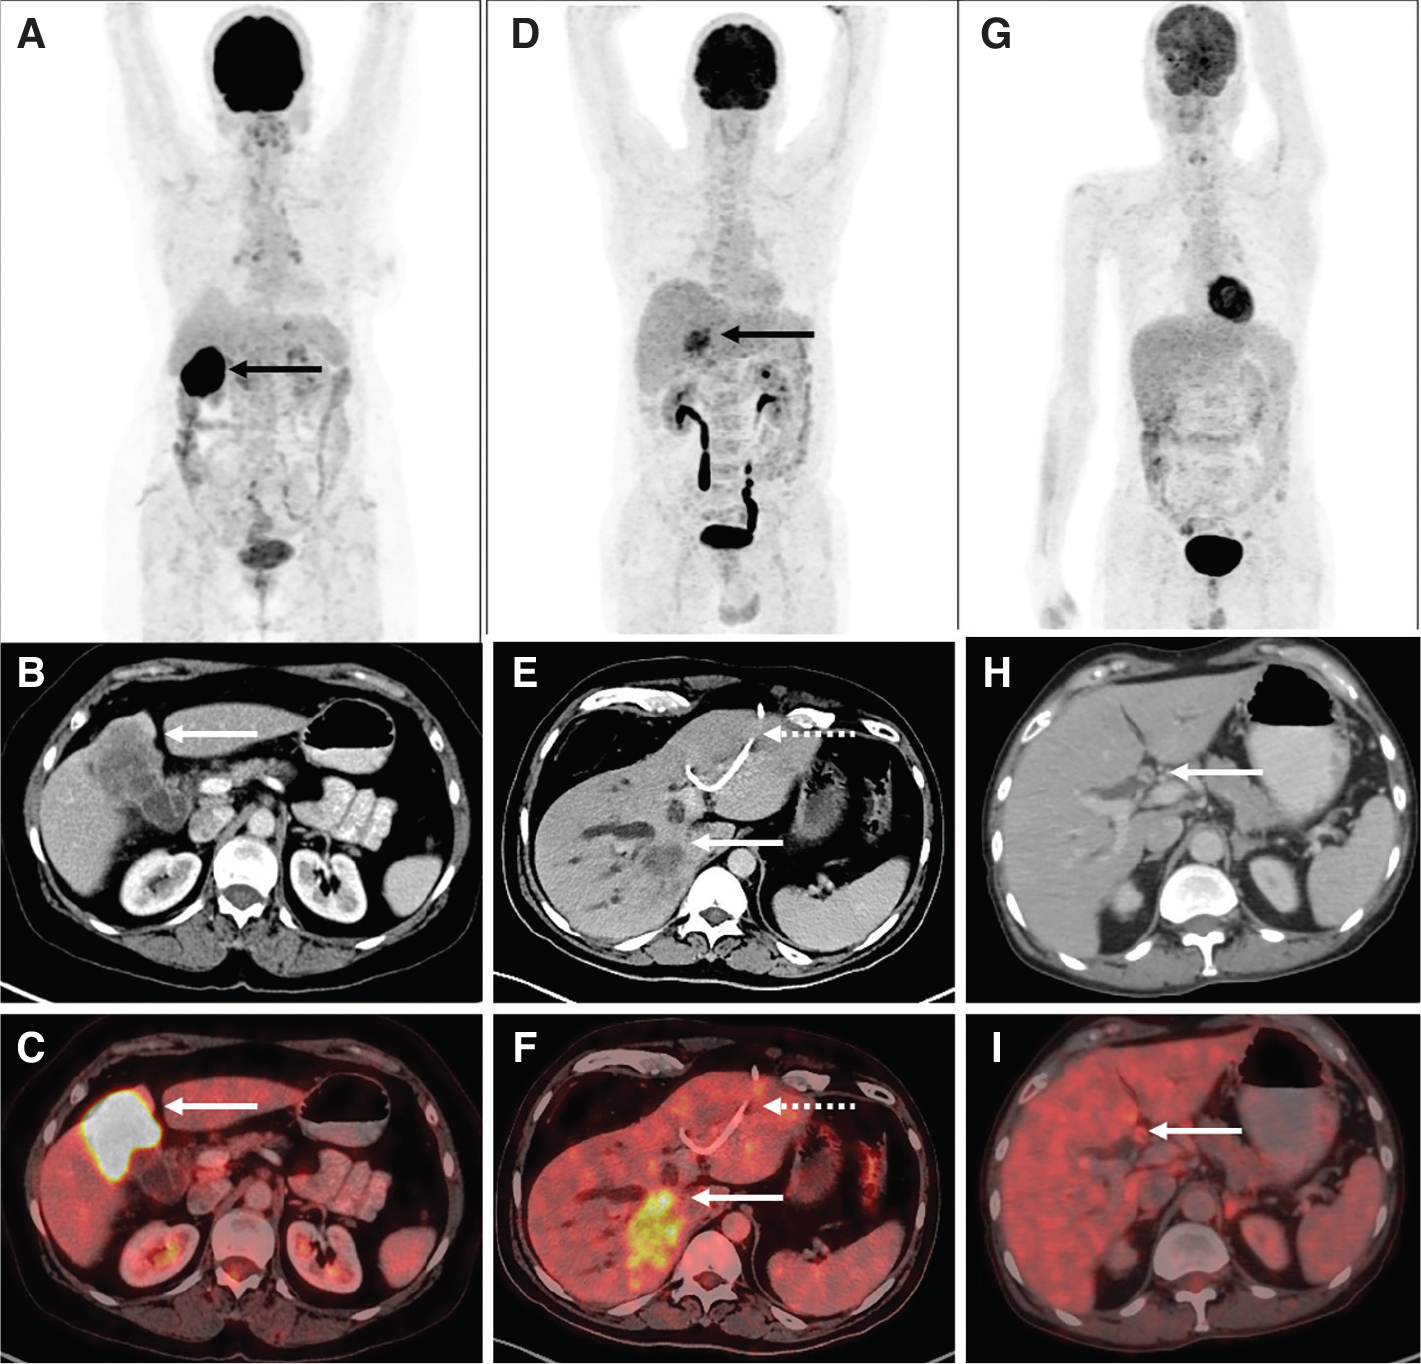

Fibroblasts associated with malignancy are known to be involved in tumor growth, migration, and progression. Fibroblast activation protein (FAP) is a serine protease highly expressed in cancer associated fibroblasts (CAF). As CAFs make about 90% of the gross tumor mass, targeting FAP inhibitor (FAPI) for imaging can aid in the visualisation of the tumor stroma. Guo et al. compared CECT, liver MRI, 68Ga-FAPI and 18F-FDG PET/CT in diagnosing primary and metastatic lesions in patients with HCC. Thirty-four individuals with hepatic lesions were included in the study and underwent concomitant 68Ga-FAPI-04, 18F-FDG PET, and CT scans. In the detection of primary liver tumors, the sensitivities of CECT, MRI, 68Ga-FAPI-04, and 18F-FDG PET/CT were found to be 96%, 100%, 96%, and 65%, respectively (19). 68Ga-FAPI PET/CT also has the potential to open the door for theranostic treatment option with therapeutic radionuclides in select patients showing 68Ga-FAPI uptake. Figure 2 (A-D) shows comparison of 18F-FDG and 68Ga-FAPI PET in a case of HCC.

Fig 1

Figure 2. 18F-FDG, 68Ga-FAPI PET/CT in HCC and 68Ga-DOTANOC PET/CT in NET. A. Maximum Intensity Projection (MIP) image of 18F-FDG PET/CT showing increased tracer uptake in the left lobe of liver in a case of HCC. Corresponding fused 18F-FDG PET/CT (B) image shows a non-FDG avid lesion in segment VII of liver (white arrow) and FDG avid lesion in left lobe. C. MIP image of 68Ga-FAPI PET/CT in the same patient showing areas of increased FAPI uptake in both lobes of the liver with corresponding fused transaxial 68Ga-FAPI PET/CT (D) image showing FAPI avidity (SUVmax 9.8) in the same segment VII and left lobe liver lesions (green arrow). 68Ga-FAPI PET can detect more lesions with higher tracer uptake compared to 18F-FDG PET-CT in HCC. E. MIP image of 68Ga-DOTANOC PET/CT in another patient with neuroendocrine tumor showing intense tracer uptake in the liver in multiple areas. Corresponding fused axial PET/CT image (F) shows intensely somatostatin receptor expressing lesions in both lobes of the liver, consistent with metastatic NET. 68Ga- DOTANOC PET/CT is highly specific for neural crest origin tumors.

Molecular imaging methods useful in diagnosis, staging and metastasis evaluation of NETs include 111In-pentetreotide somatostatin receptor scintigraphy (111In-SRS), 68Ga-DOTATATE, 68Ga-DOTANOC, and 18F-DOPA PET/CT for well-differentiated tumors and 18F-FDG PET/CT for high grade tumors. Somatostatin receptor (SSTR) overexpression is present in 60–90% of these tumors and is an essential mechanism for SRS. Of these, somatostatin receptor subtype 2 is expressed by 85% of NETs. Recent experience with 68Ga-labeled somatostatin analogue PET imaging shows higher sensitivity as compared to 111In-SRS and 99mTc-SRS. 111In-SRS and 99mTc-SRS are used less due to lower sensitivity and resolution compared to 68Ga-DOTA-NOC/TATE PET/CT. The diagnostic efficacy of 68Ga-DOTATATE PET/CT was compared to that of 99mTc-octreotide SPECT/CT and CT/MRI by Fallahi et al. In this prospective study, 25 NET patients who had been referred for an octreotide scan for suspected or proven NET were included. On a patient-based analysis, the sensitivity for CT/MRI, 68Ga-DOTATATE PET/CT, and 99mTc-octreotide SPECT/CT, respectively, was 71%, 90%, and 65%. The specificity of 99mTc-octreotide SPECT/CT, 68Ga-DOTATATE PET/CT, and CT/MRI was 80%, 80%, and 75%, respectively (21). Figure 2 (E-F) shows 68Ga-DOTANOC PET/CT images in a case of metastatic well-differentiated NET.